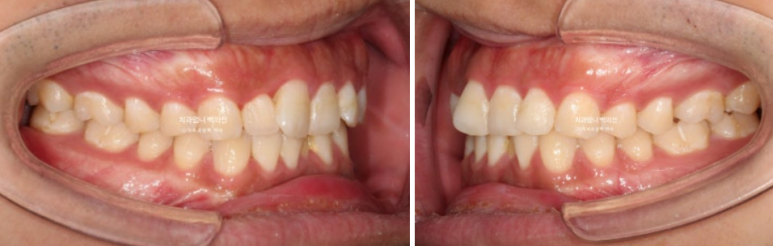

어금니교합은 좋은 편입니다.

치료시작 4개월째 모습입니다.

배열이 거의 완료되었습니다.

25년 6월, 5개월만에 치료를 마무리 했습니다.

25.06

원래 좋았던 교합은 잘 유지가 되었습니다.